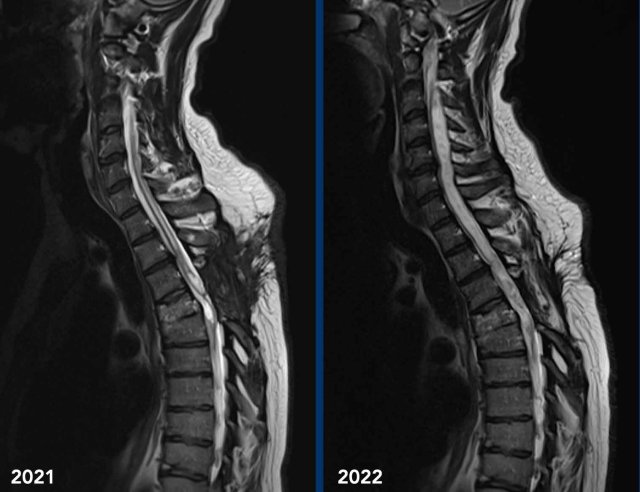

These images are of a 45-year old man who had a traumatic cord injury at the level of T4-5 some years ago.

He now presents with progressive pain in the legs with decreased reflexes in both arms and legs and a bilateral Horner.

Images

Sagittal T2 TSE weighted images in 2021 of the cervicothoracic spine show loss of height of verterbra T4 with cord dissection and a cystic myelomalacia at this level and surrounding syringohydromyelia.

In 2022 sagittal T2W images of the cervicothoracal spine show progressive syringohydromyelia.

Continue with the next images...

The Horner syndrome can be explained by the progressive syringohydomyelia at the cervical level with disruption of the first order neurons of the oculosympathetic pathway.